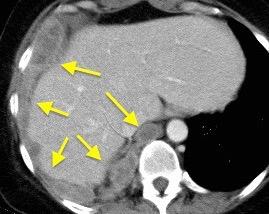

T. mixto de células germinales del testículo izquierdo

Nódulos pulmonares múltiples. (flechas verdes). Masas paratraqueales. (flechas amarillas). Dudoso ensanchamiento retrocrural (flechas negras). sigue….

Ttawfik A et al. Trans-diaphragmatic Pathologies: Anatomical Background and Spread of Disease on cross-sectional Imaging. Current Problems in Diagnostic Radiology. 2021.

T. mixto de células germinales del testículo

izquierdo Metástasis pulmonares. (flechas verdes). Ganglios paratraqueales. (flechas amarillas). Ganglios retroperitoneales (flechas negras)

Tawfik A et al. Trans-diaphragmatic Pathologies: Anatomical Background and Spread of Disease on cross-sectional Imaging. Current Problems in Diagnostic Radiology. 2021.